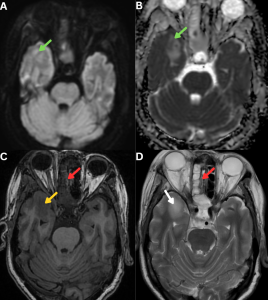

Fig 12: Clinical history:

A 58-year-old diabetic male presented with progressive visual loss, facial numbness, and cranial nerve deficits.

Figure A:

Axial FLAIR MRI image demonstrates T2/FLAIR hyperintensity involving the posterior aspects of the optic tracts, optic chiasm, and optic radiations (red arrows).

Figure B:

Axial post-contrast T1-weighted MRI image demonstrates peripheral enhancement along the posterior aspects of both optic nerves (orange arrows), supporting perineural involvement in invasive fungal infection.

Figure C:

Axial FLAIR MRI image demonstrates T2/FLAIR hyperintensity within the pons, predominantly at the trigeminal nerve root entry zones, more pronounced on the right (green arrows).

Figure D:

Axial post-contrast T1-weighted MRI image demonstrates peripheral enhancement of the bilateral trigeminal nerves involving their cisternal segments and Meckel’s caves, consistent with perineural extension of mucormycosis.